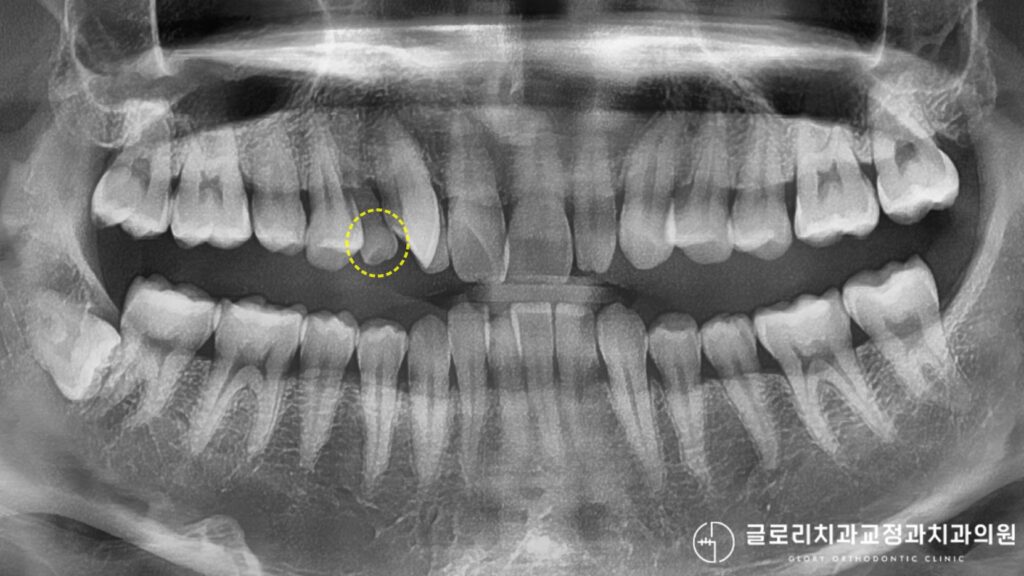

과잉치인 줄 알았는데 잔존유치? 망우동 교정치과 정밀 검사의 중요성

치아가 삐뚤빼뚤하게 배열되어 있고, 그 사이에 작은 이가 하나 더 있는 것처럼 보인다면 많은 분들이 ‘과잉치’를 의심하게 됩니다.

과잉치란 정상적인 개수보다 더 많이 존재하는 치아를 말하는데요.

그런데 정밀 검사를 해보면 과잉치가 아니라 빠져야 할 시기를 놓친 유치, 즉 잔존유치인 경우가 있습니다.

겉으로 보기에는 과잉치처럼 보일 수 있지만, 엑스레이 촬영과 정밀 검사를 통해 확인하면 그 정체를 정확히 알 수 있습니다.

망우동 교정치과 예시자료인 엑스레이 상에서 뿌리의 형태를 보면 유치인지 영구치인지 구분할 수 있고, 주변에 매복되어 있는 영구치가 있는지도 파악 가능합니다.

이처럼 육안으로만 판단하기 어려운 상황을 정밀하게 분석하여 불필요한 발치를 방지합니다.

잔존유치의 경우 상태에 따라 유지할 수도 있고, 제거 후 공간을 활용할 수도 있기 때문에 정확한 진단이 우선되어야 합니다.